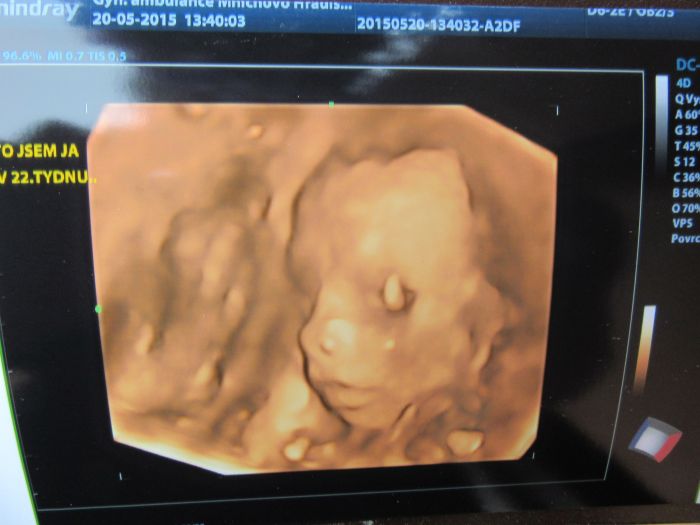

Ahojky, tak dneska jsme byli s manželem na 3D a máme potvrzenou malou fešandu. I přesto, že jsme si přáli kluka tak nakonec jsem spokojená, že to bude holčička. Doktor nám taky řekl, že je vše v pořádku a to je to hlavní. Přikládám fotečky, jsem z malý opravdu nadšená.

[744686] jakoby se na tebe divala, krásné!

kacenko to je fakt nadherna fotecka ,jak je tam krasne videt no uzasny:-) gratuluji k holcicce